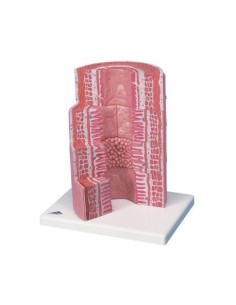

Des modèles anatomiques détaillés pour tous les besoins

Du crâne en 22 parties à verrouillage magnétique aux modèles de colonne vertébrale, des modèles d'articulation aux modèles de cœur, chaque pièce de notre collection est conçue pour une immersion totale dans l'étude de l'anatomie humaine. Nos modèles, réalisés à partir de scans d'os réels, garantissent une expérience tactile authentique et une fidélité de poids presque identique aux originaux.

Des outils pédagogiques innovants pour l'enseignement et la pratique de la médecine

Indispensables aux étudiants comme aux professionnels, nos modèles anatomiques sont des outils pédagogiques qui permettent d'observer les structures anatomiques avec précision, en évitant les dissections ou les études invasives. Ils sont également utiles pour expliquer les pathologies aux patients, ce qui rend la communication plus efficace et permet de gagner un temps précieux.